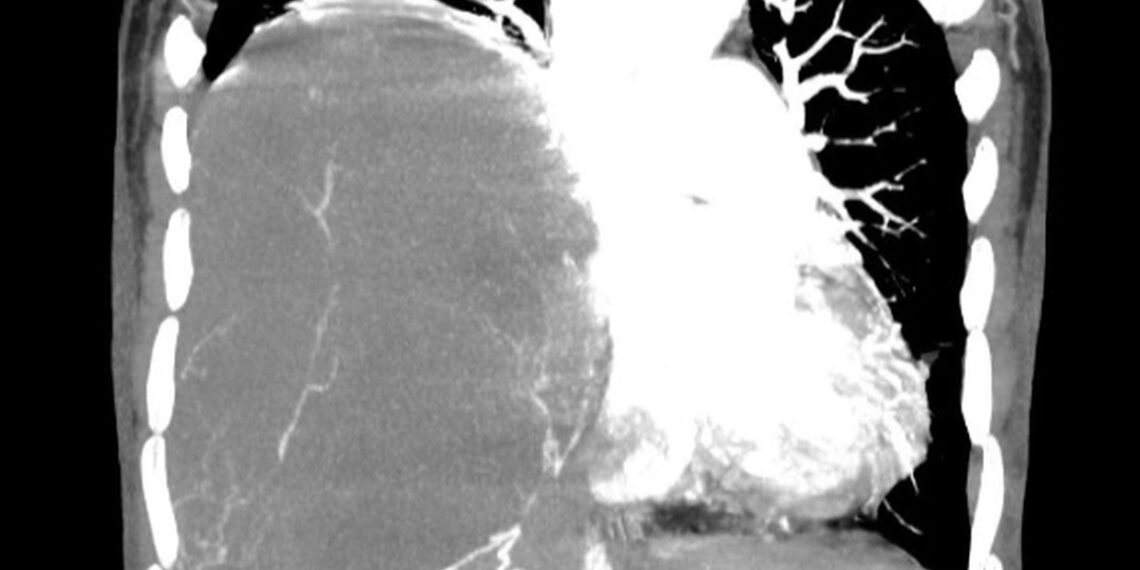

Kết quả chụp cắt lớp vi tính tại Bệnh viện Ung Bướu Hà Nội cho thấy, lồng ngực phải bệnh nhân có khối đặc kích thước 20x15cm đè xẹp phổi, thâm nhiễm trung thất, thành ngực.

Hình ảnh khối u choán hết khoang lồng ngực của bệnh nhân (Ảnh: Bệnh viện cung cấp).